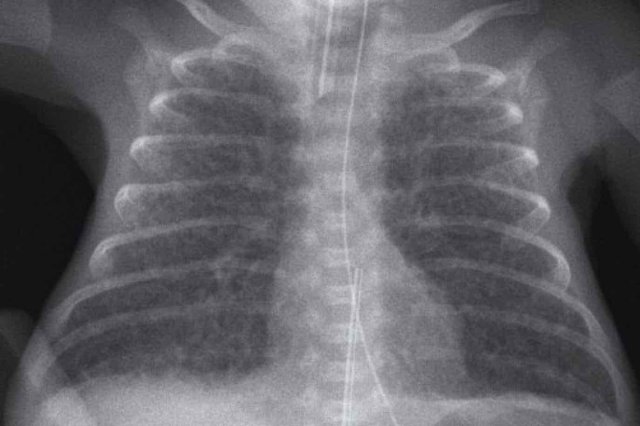

One day old neonate, 26 weeks of gestational age.

Image

• Granular opacification of both lungs.

• Vessels and cardiac silhouette are hard to distinguish.

• Umbilical venous line properly positioned.

• Deep position of umbilical artery line, which should be pulled back to the level of T6.

• NG tube in situ.

Conclusion: RDS grade 3.